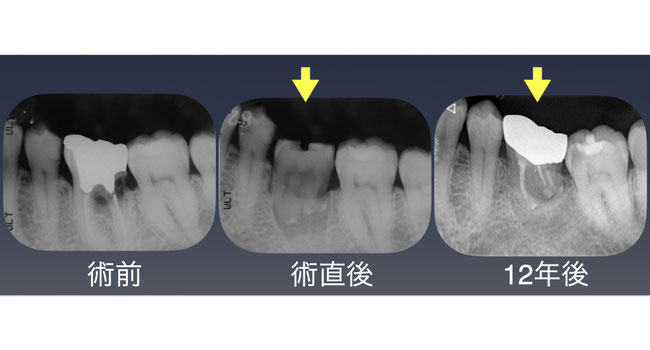

左下第一大臼歯の深い箇所に大きな虫歯を認め保存不可能。骨の量は十分あるためインプラントでの機能回復も可能であったが上顎に機能していない親知らずがあったので歯牙移植を行った。

移植当時当院にはCT撮影装置がなかったために術前に親知らずの細かい歯根形態は確認できなかった。抜歯してみると親知らずの歯根は大きく曲がっており左下第一大臼歯抜歯部に収めることができなかったために口の外で移植する親知らずの根をカットし逆根管充填も行ったのちに移植した。骨の中に収まる歯根部分が短くなり予後に不安があったが12年経過した現在でも全く問題なく機能している。